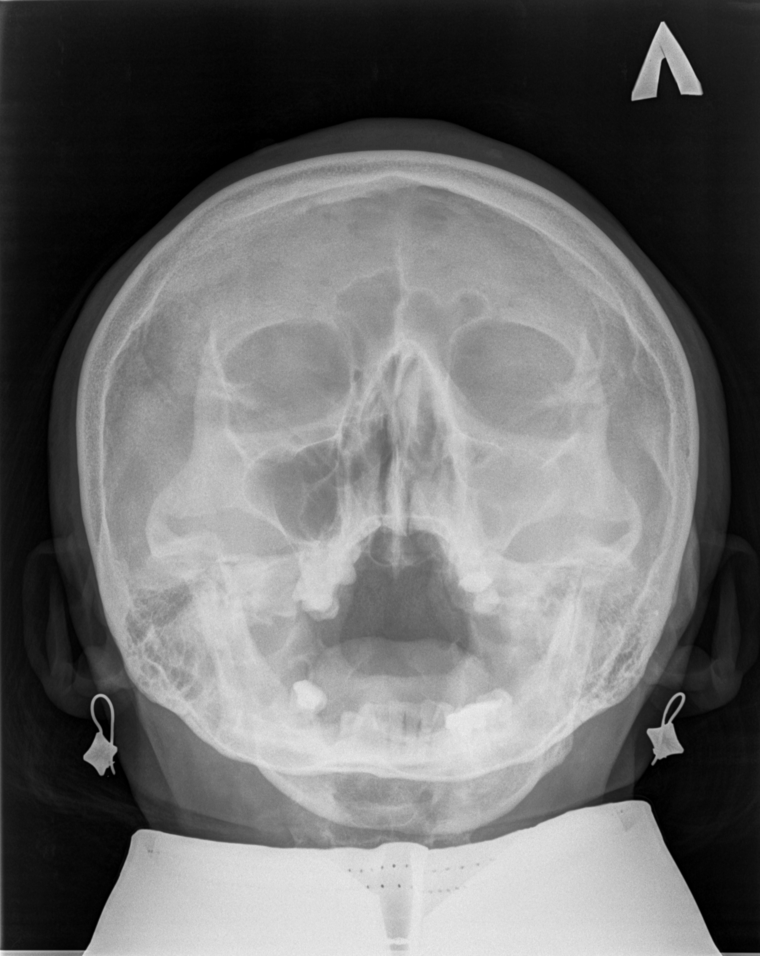

ИИ и умные алгоритмы для анализа рентгеновских снимков черепа. Обнаружение синусита и процента заполненности пазух носа менее чем за 30 секунд